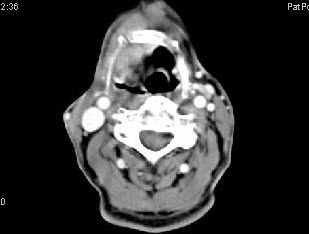

男,63岁,咽喉部不适约一年,近2个月经常咳嗽,痰中带有血丝,CT如图所示,应诊断为()。

A、梨状窝癌

B、声门型喉癌

C、声门下型喉癌

D、声门上型喉癌

E、混合型喉癌

正确答案:

D